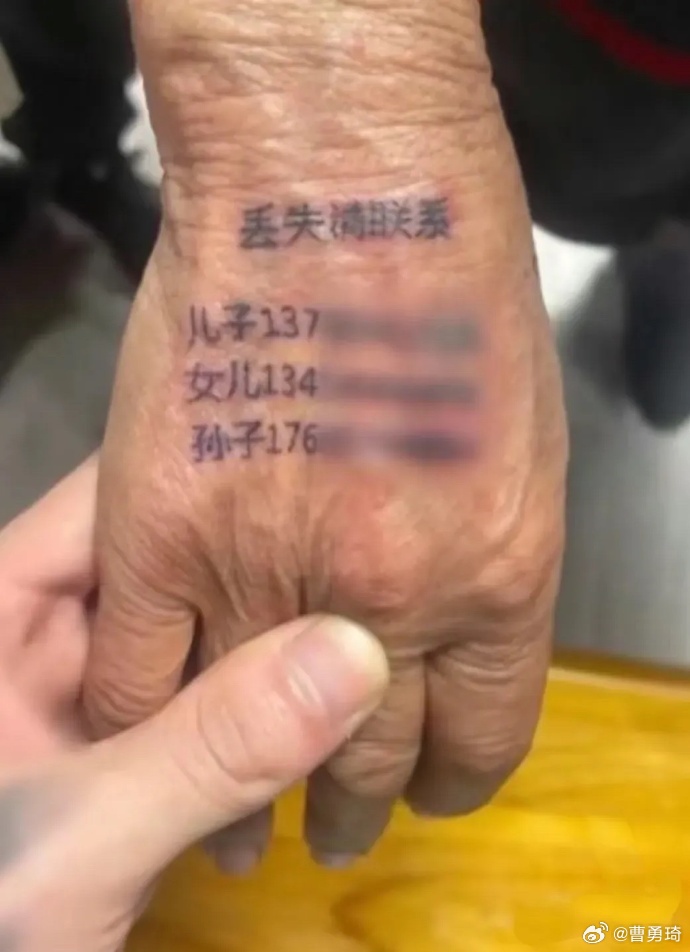

有些爱忘事的人想到了自己,不禁打了个寒颤。